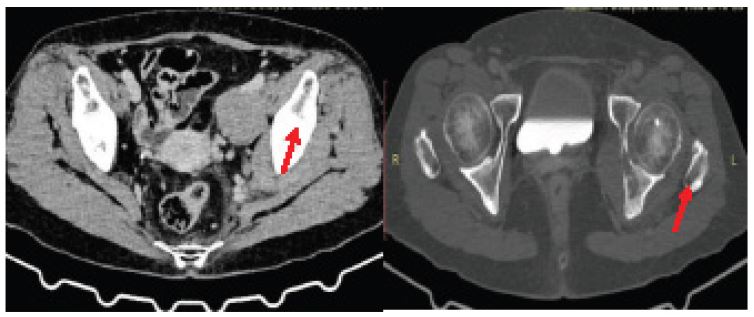

After EGD, the patient had one episode of melena, which was likely a residual without reported recurrence thereafter. Patient was clinically improving and discharged with oral proton pump inhibitors and was advised for follow-up with histopathology report. There was no recurrence of the gastrointestinal bleeding. On follow-up, histopathology of the gastric ulcers revealed atypical lymphoid proliferation with no dysplasia or intestinal metaplasia. The specimens were sent for immunohistochemical staining and the patient was advised to undergo Whole Abdomen Computed Tomography (CT) scan with IV contrast to further evaluate the findings in the whole abdomen ultrasound. CT scan of the whole abdomen revealed an intramuscular mass, at the left obturator internus muscle with lytic changes in the adjacent ischium and acetabulum with ipsilateral pelvic lymphadenopathies, gastric wall thickening was also reported suggestive of gastritis with gastric ulcer, at the proximal body (Figure 3). The immunohistochemical stains showed that the atypical cells stained positive for CD20, with 80-90% expression of BCL2 and ki-67 and negative for CD10 and CD3. These findings support the diagnosis of a primary diffuse large B-cell lymphoma (Figure 4). The patient was then referred to a Medical Oncologist.

Image is Not Display Check it

Figure 3: Intramuscular mass on the left obturator internus muscle with lytic changes in the adjacent ischium acetabulum with ipsilateral pelvic lymphadenopathies.

Ct-Scan whole abdomen (11/10/23)

1. Intramuscular Mass, Left Obturator Internus Muscle with Lytic Changes In The Adjacent Ischium and Acetabulum with Ipsilateral Pelvic Lymphadenopathies

2. Simple Hepatic Cyst, Segment 3

3. Gastric Wall Thickening Suggestive Of Gastritis With Gastric Ulcer, Proximal Body

4. Simple Renal Cortical Cyst, Left (Bosniak 1)

5. Senile Osteoporosis

6. Thoracolumbar Spondylosis

7. Incidental Note Of Minute Pulmonary Nodule, Medial Basal

Segment, Right Lower Lobe (Too Small To Characterize)